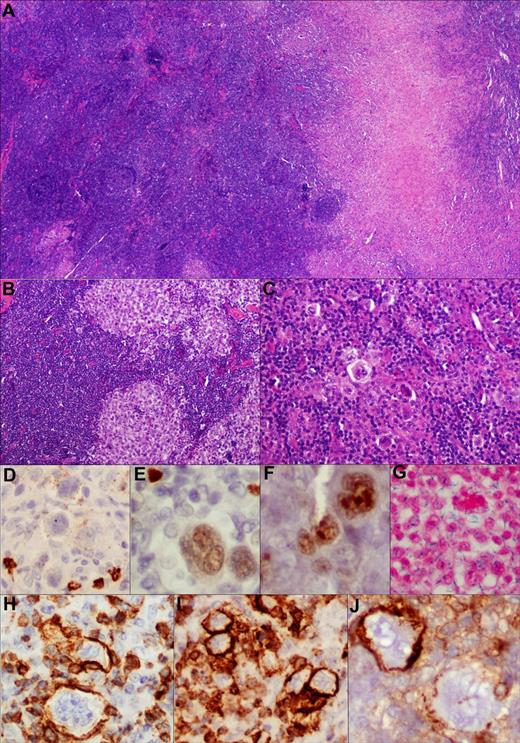

Composite lymphoma comprising cHL and follicular lymphoma. TCA in cHL component. (A) Low-power view of the composite histologic components (H&E, ×100). (B,C) Higher-power view depicting morphologically distinct components; ie, follicular lymphoma grade 3 and cHL, respectively (H&E, ×200). (D-J) Various markers expressed within the HRS cell component with very weak and variable CD20 (D), PAX-5 (E), and BCL-6 (F) expression (immunoperoxidase, ×200, ×400, ×400). (G) These cells are EBER negative (in situ hybridization, ×400). (H-J) TCA expression in cHL component. Among the T-cell markers, there is strong CD3 (H), CD2 (I), and CD4 (J) expression on membrane of the HRS cells (immunoperoxidase, ×400, ×400, ×400). Notably, CD4 was variable in this case with adjoining scattered CD4-negative HRS cells, lending credence to the specificity of staining.